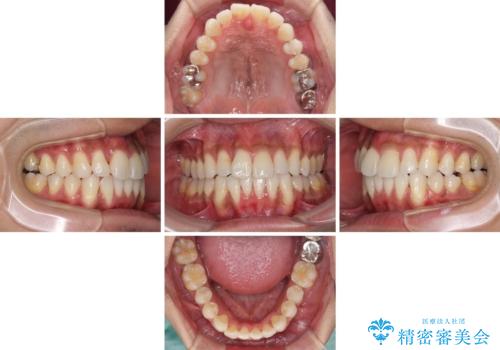

上顎の狭い歯列をインビザラインで拡大

- 上下前歯の叢生を気にして来院された患者様です。

奥歯はクロスバイトとなっているので上顎は側方拡大を行いつつ、上下全体の叢生をインビザラインにより改善することとしました。

治療途中でクリーニングやホワイトニングを行い、歯列が整うと同時に明るい口元となりました。